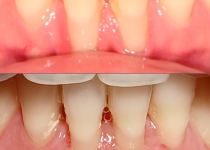

잘못된 교정치료로 발생한 잇몸퇴축 잇몸이식